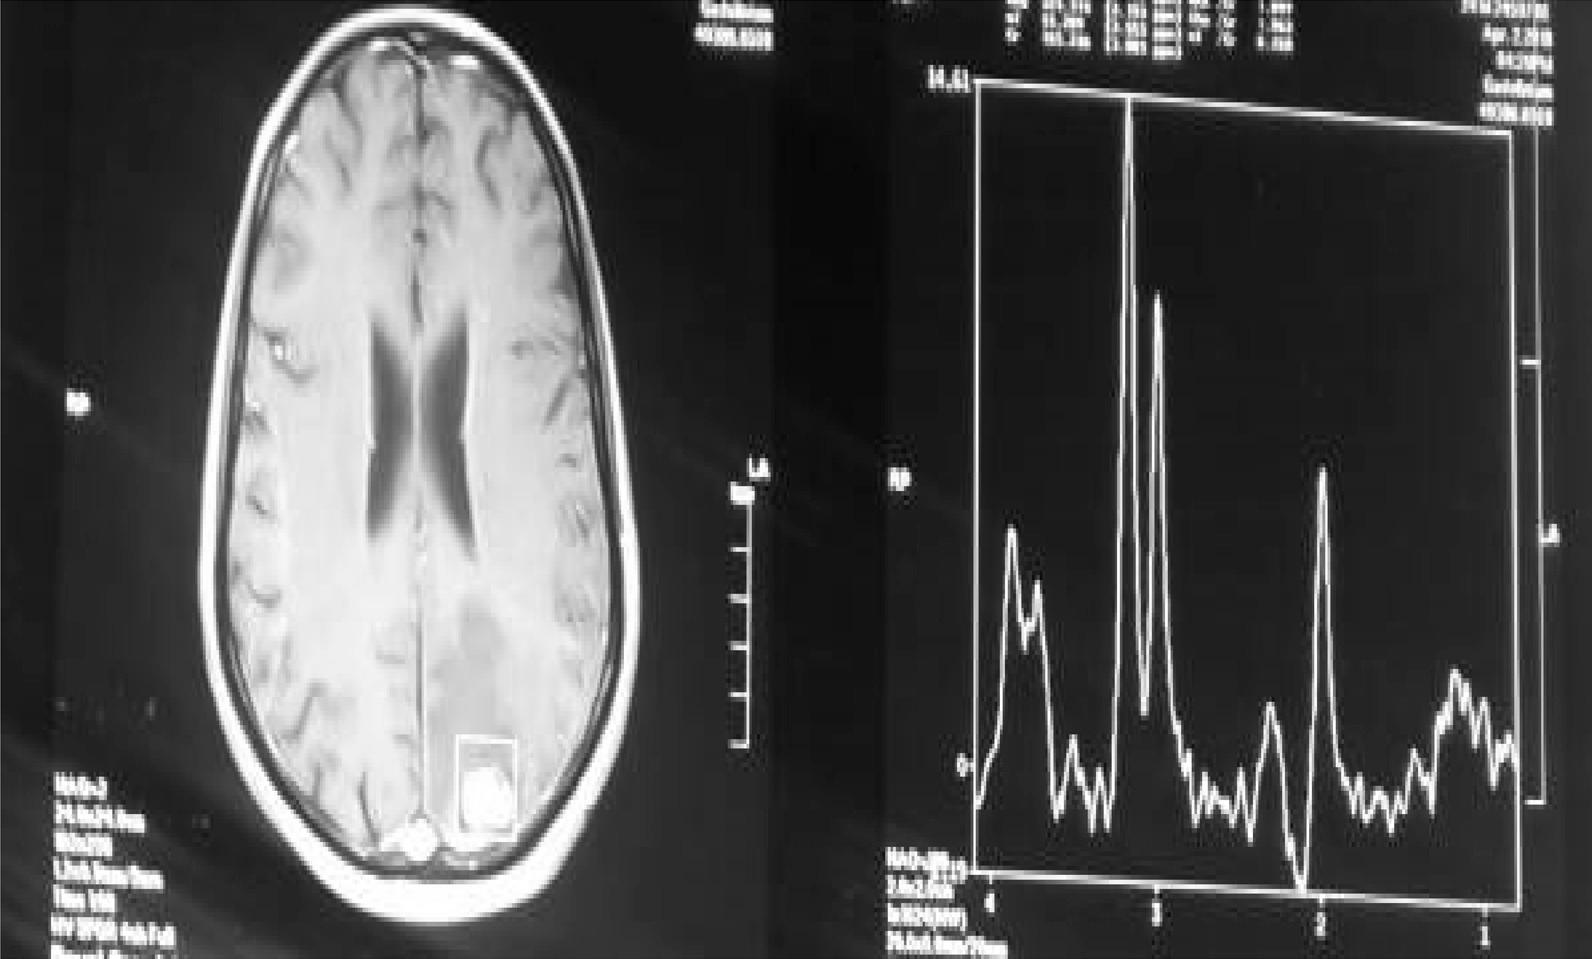

A 24-year-old, previously healthy Afro-asiatic man presented to our neurosurgical outpatient clinic complaining of headache and an attack of convulsions. On examination, he had bilateral lower limb weakness more on the right side. Laboratory investigations including stool and urine general test results were unremarkable. Magnetic resonance imaging of the brain was performed and showed an intra-axial left parietal mass; a granulomatous lesion was suggested in the differential diagnoses. The patient underwent craniotomy and total resection of the lesion. Histopathology confirmed the presence of active cerebral Schistosoma mansoni infection. Orally administered praziquantel was initiated at a dose of 20 mg/kg twice a day for a total of 3 days along with oral administration of corticosteroids for 2 weeks. The patient improved postoperatively without residual weakness and with no further convulsions.

一名 24 岁、既往健康的非裔亚洲男性因头痛和癫痫发作到我们的神经外科门诊就诊。体格检查发现他的双侧下肢无力,右侧更为明显。包括粪便和尿液常规检查在内的实验室检查结果无明显异常。对大脑进行磁共振成像检查,显示左顶叶脑内轴内肿块;鉴别诊断中提示为肉芽肿性病变。患者接受了开颅手术和病变的完全切除。组织病理学证实存在活动性脑曼氏血吸虫感染。给予患者口服吡喹酮,剂量为 20mg/kg,每日 2 次,共 3 天,并同时口服皮质类固醇 2 周。患者术后恢复良好,无残留无力和进一步的癫痫发作。